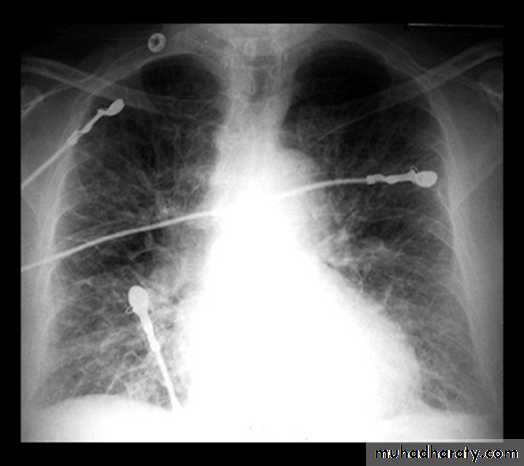

BNP brain natriuretic pepetideChest X-ray in Heart Failure

CardiomegalyCephalization of the pulmonary vessels

Pleural effusions

Cardiomegaly Pulmonary vessel congestion